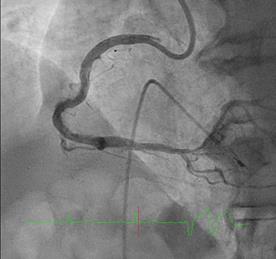

Can thiệp động mạch vành qua da

Một số từ chuyên ngành nên biết Catheter      Một loại ống thông nhỏ làm bằng chất liệu nhựa dẻo đặc biệt, thường sử dụng trong can thiệp động mạch vành qua da. Stent           Giá đỡ bằng kim loại đặc biệt, giúp lòng mạch giảm khả năng tái hẹp; có 2...